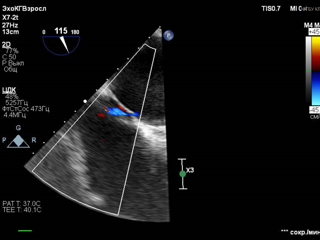

Лабораторные анализы, хотя и неспецифичны, необходимы для исключения других заболеваний. Инструментальные методы, особенно эхокардиография, играют ключевую роль в подтверждении диагноза. Трансэзофагеальная эхокардиография обладает высокой точностью в выявлении дефекта. В отдельных ситуациях может потребоваться инвазивная диагностика, например, катетеризация правых отделов сердца. При установлении диагноза важно провести дифференциальную диагностику, чтобы исключить другие возможные причины мигреней, инсульта и тромбоэмболических осложнений.

Как проводится хирургическое лечение открытого овального окна? Транскатетерное закрытие аномалии межпредсердной перегородки осуществляется с применением специализированных окклюдерных систем. Процедура проводится под контролем рентгеноскопии и эхокардиографии. Методика включает введение катетера с окклюзионной конструкцией через бедренную вену до достижения правого предсердия. После позиционирования устройства оно раскрывается и надежно фиксируется по обе стороны дефекта в межпредсердной перегородке, обеспечивая эффективное закрытие овального отверстия. В Волынской больнице специалисты первого кардиологического отделения и отделения рентгенохирургических методов диагностики и лечения проводят подготовку и выполняют данный вид хирургического эндоваскулярного вмешательства.